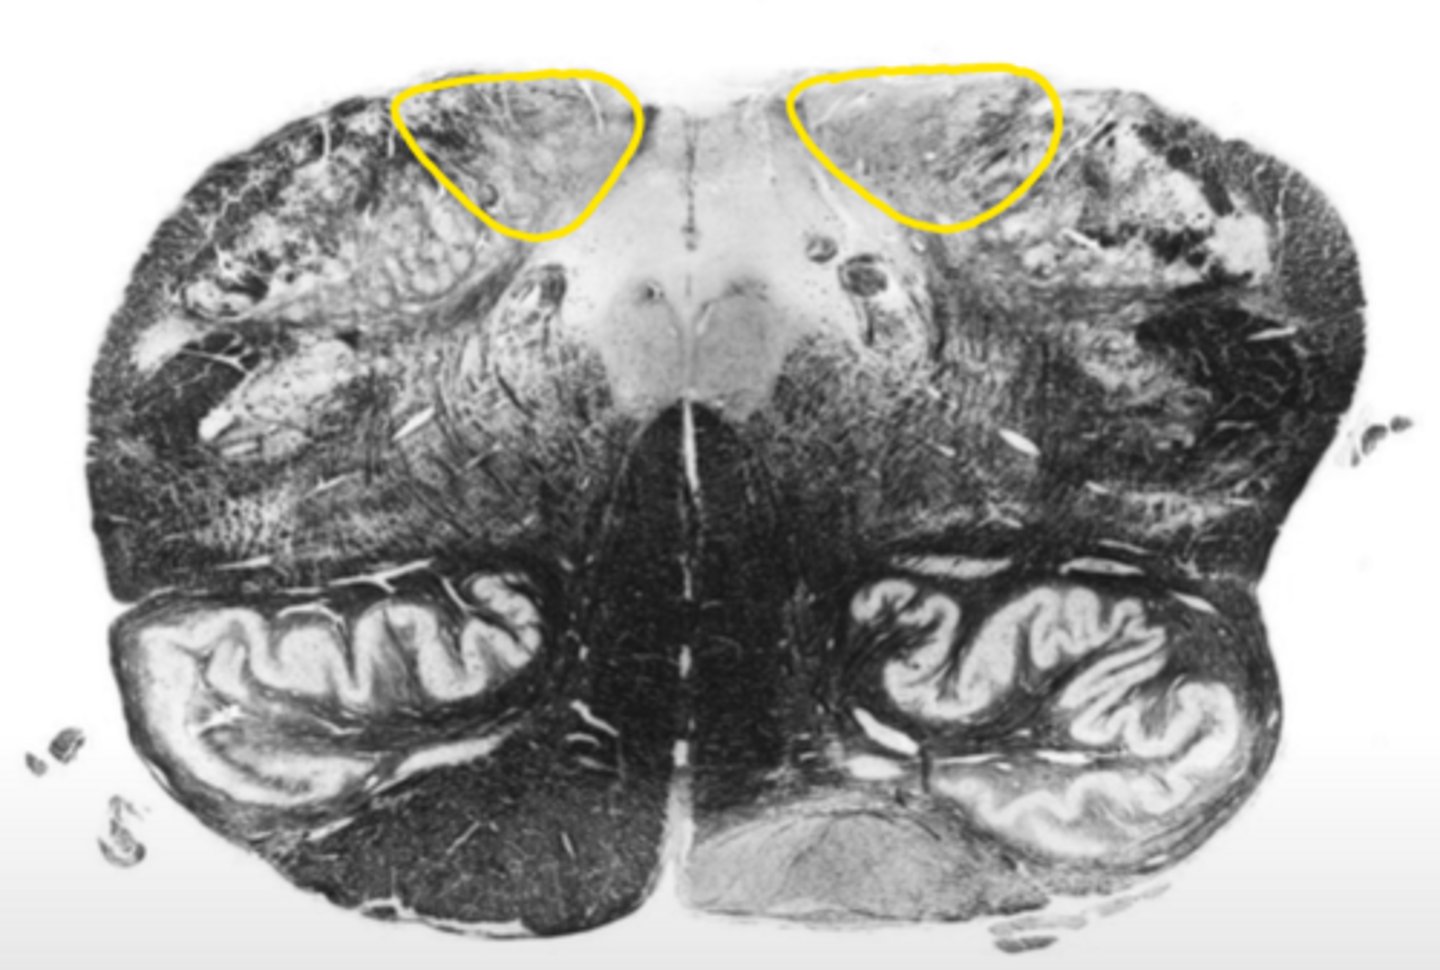

corticospinal fibers

ID the structure